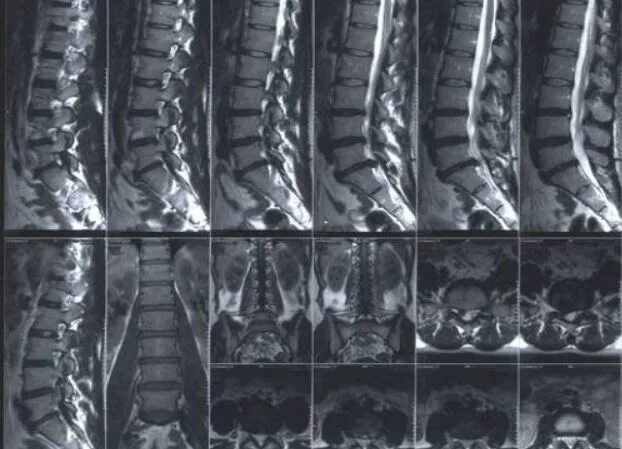

Мрт шейно поясничного отдела